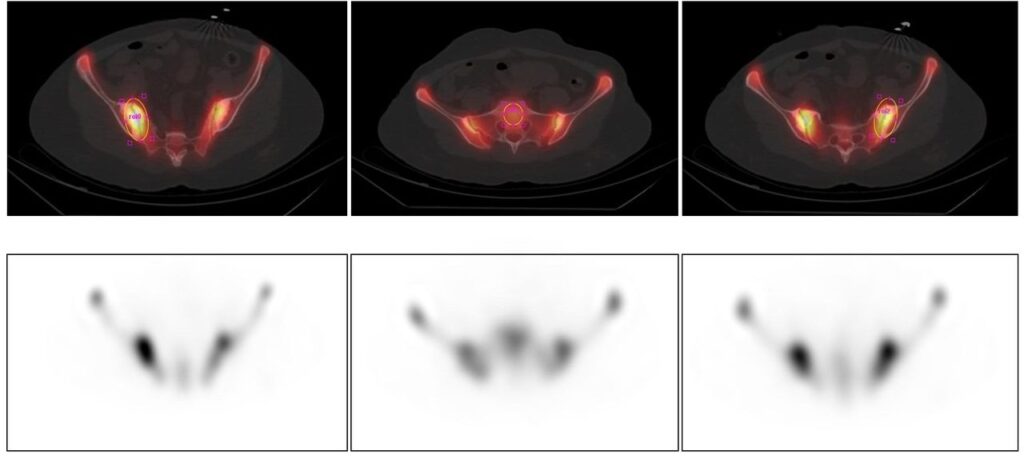

Metodi di quantificazione dell’uptake miocardico nell’amiloidosi cardiaca.

Immagini planari total body in proiezione anteriore che illustrano diverse metodiche di posizionamento delle ROI per l’analisi quantitativa della captazione. (A) ROI cardiaca (rossa), ROI sugli organi escretori (reni e vescica, verdi) all’interno di una ROI total body rettangolare. (B) Disposizione simile alla A, ma con la ROI total body sagomata in modo preciso sul profilo del paziente. (C) ROI cardiaca (rossa) e ROI pelvica (blu) per il calcolo del rapporto Cuore/Pelvi. (D) ROI cardiaca (rossa) e ROI sulla teca cranica (quadrato blu) per il calcolo del rapporto Cuore/Cranio (Heart-to-Skull ratio). (E, F) ROI cardiaca posizionata sull’emitorace sn (rossa) e ROI circolare speculare sull’emitorace destro (nera) per il calcolo del rapporto Cuore/Controlaterale (Heart-to-Contralateral ratio, H/CL). Nel pannello E sono tracciate ulteriori piccole ROI addominali per la stima del fondo tissutale (background).